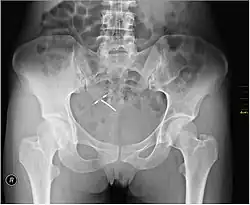

An IUD as seen on pelvic X ray

Most copper IUDs have a T-shaped frame that is wound around with pure electrolytic copper wire and/or have copper collars (sleeves). The arms of the frame hold the IUD in place near the top of the uterus. The Paragard TCu 380a measures 32 mm (1.26") horizontally (top of the T), and 36 mm (1.42") vertically (leg of the T). Copper IUDs have a first-year failure rate ranging from 0.1 to 2.2%.[46] They work by damaging sperm and disrupting their motility so that they are not able to fertilize an egg. Specifically, copper acts as a spermicide within the uterus by increasing levels of copper ions, prostaglandins, and white blood cells within the uterine and tubal fluids.[6][47] The increased copper ions in the cervical mucus inhibit the sperm's motility and viability, preventing sperm from traveling through the cervical mucus, or destroying it as it passes through.[48] Copper can also alter the endometrial lining, and while studies show that this alteration can prevent implantation of a fertilized egg ("blastocyst"), it cannot disrupt one that has already been implanted.[49]